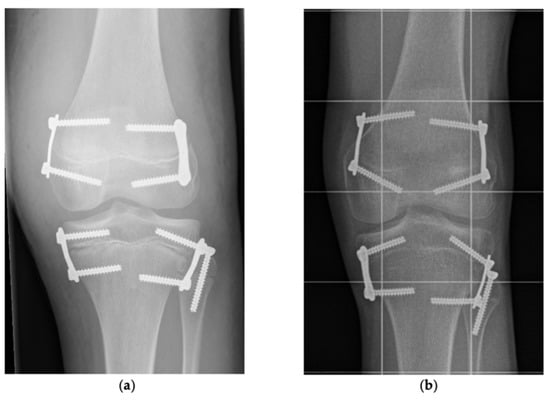

2.2. Indication, Operative Technique, and Applied Implants

2.3. Implants Applied for Epiphysiodesis